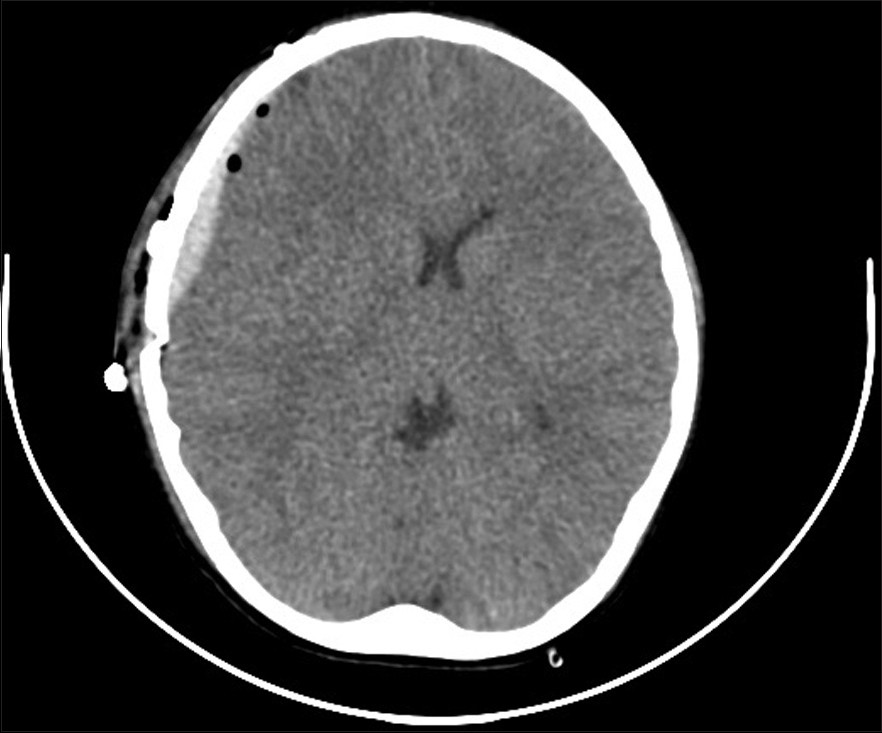

The patient was examined and found to be neurologically intact following completion of surgery. Postoperative head CT was stable and demonstrated mild edema in the region of dissection. Graft patency was ensured with biphasic signal on a bedside Doppler ultrasound [Figure 4].